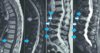

88

¿Qué tipo de traumatismo es este?

Raquimedular en RM